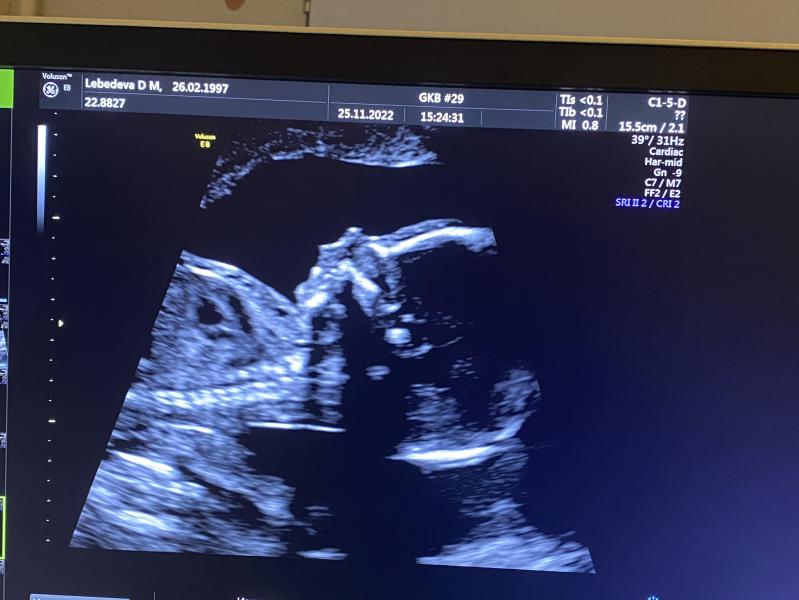

Мне 24 года… вторая(третья) долгожданная беременность… в июле этого года произошёл выкидыш на сроке 7 недель… потом свадьба.. потом гулянки.. потом празднования и хоп… замечаю задержку… и вот.. чудо после выкидыша… гематомы кровотечения и тд… и долгожданная вторая беременность

ждём тебя, Маюша 😍🙏 с Богом 🤫🤫🤫🥲😍🥹